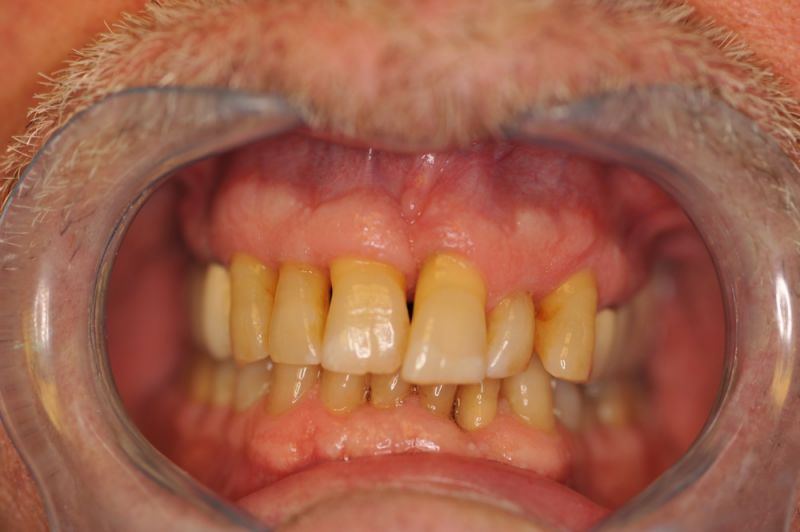

73 jähriger CMD-Patient im Recall

Der Patient hat vor 5 Jahren eine äußerst umfangreiche und komplexe CMD-Behandlung abgesclossen und befindet sich seitdem in einem engmaschigen vierteljährlichen Recall!

Seit 5 Jahren ist der Zustand des Patienten vollkommen unverändert!

Die aktuellen Taschentiefen liegen bei 2 Millimeter! Auch im Bereich der Implantate!

Auch in diesem Fall zeigt sich, dass es gerade bei älteren Patienten sinnvoll ist umfangreiche, festsitzende Versorgungen umzusetzen, so lange sich der Patient noch in einer gesundheitlich guten Konstitution befindet, um dann für die kommenden Lebensjahre Substanz vorzufinden, mit der man "arbeiten" kann.